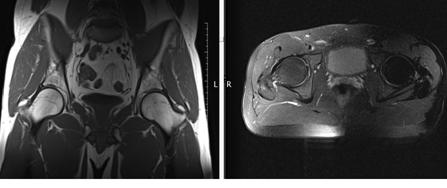

Примеры снимков представлены на рисунке 3.2 и 3.3.

Рис. 3.2 - ЛСМА (инсульт)

Рис. 3.3 - Тазобедренные суставы (норма)